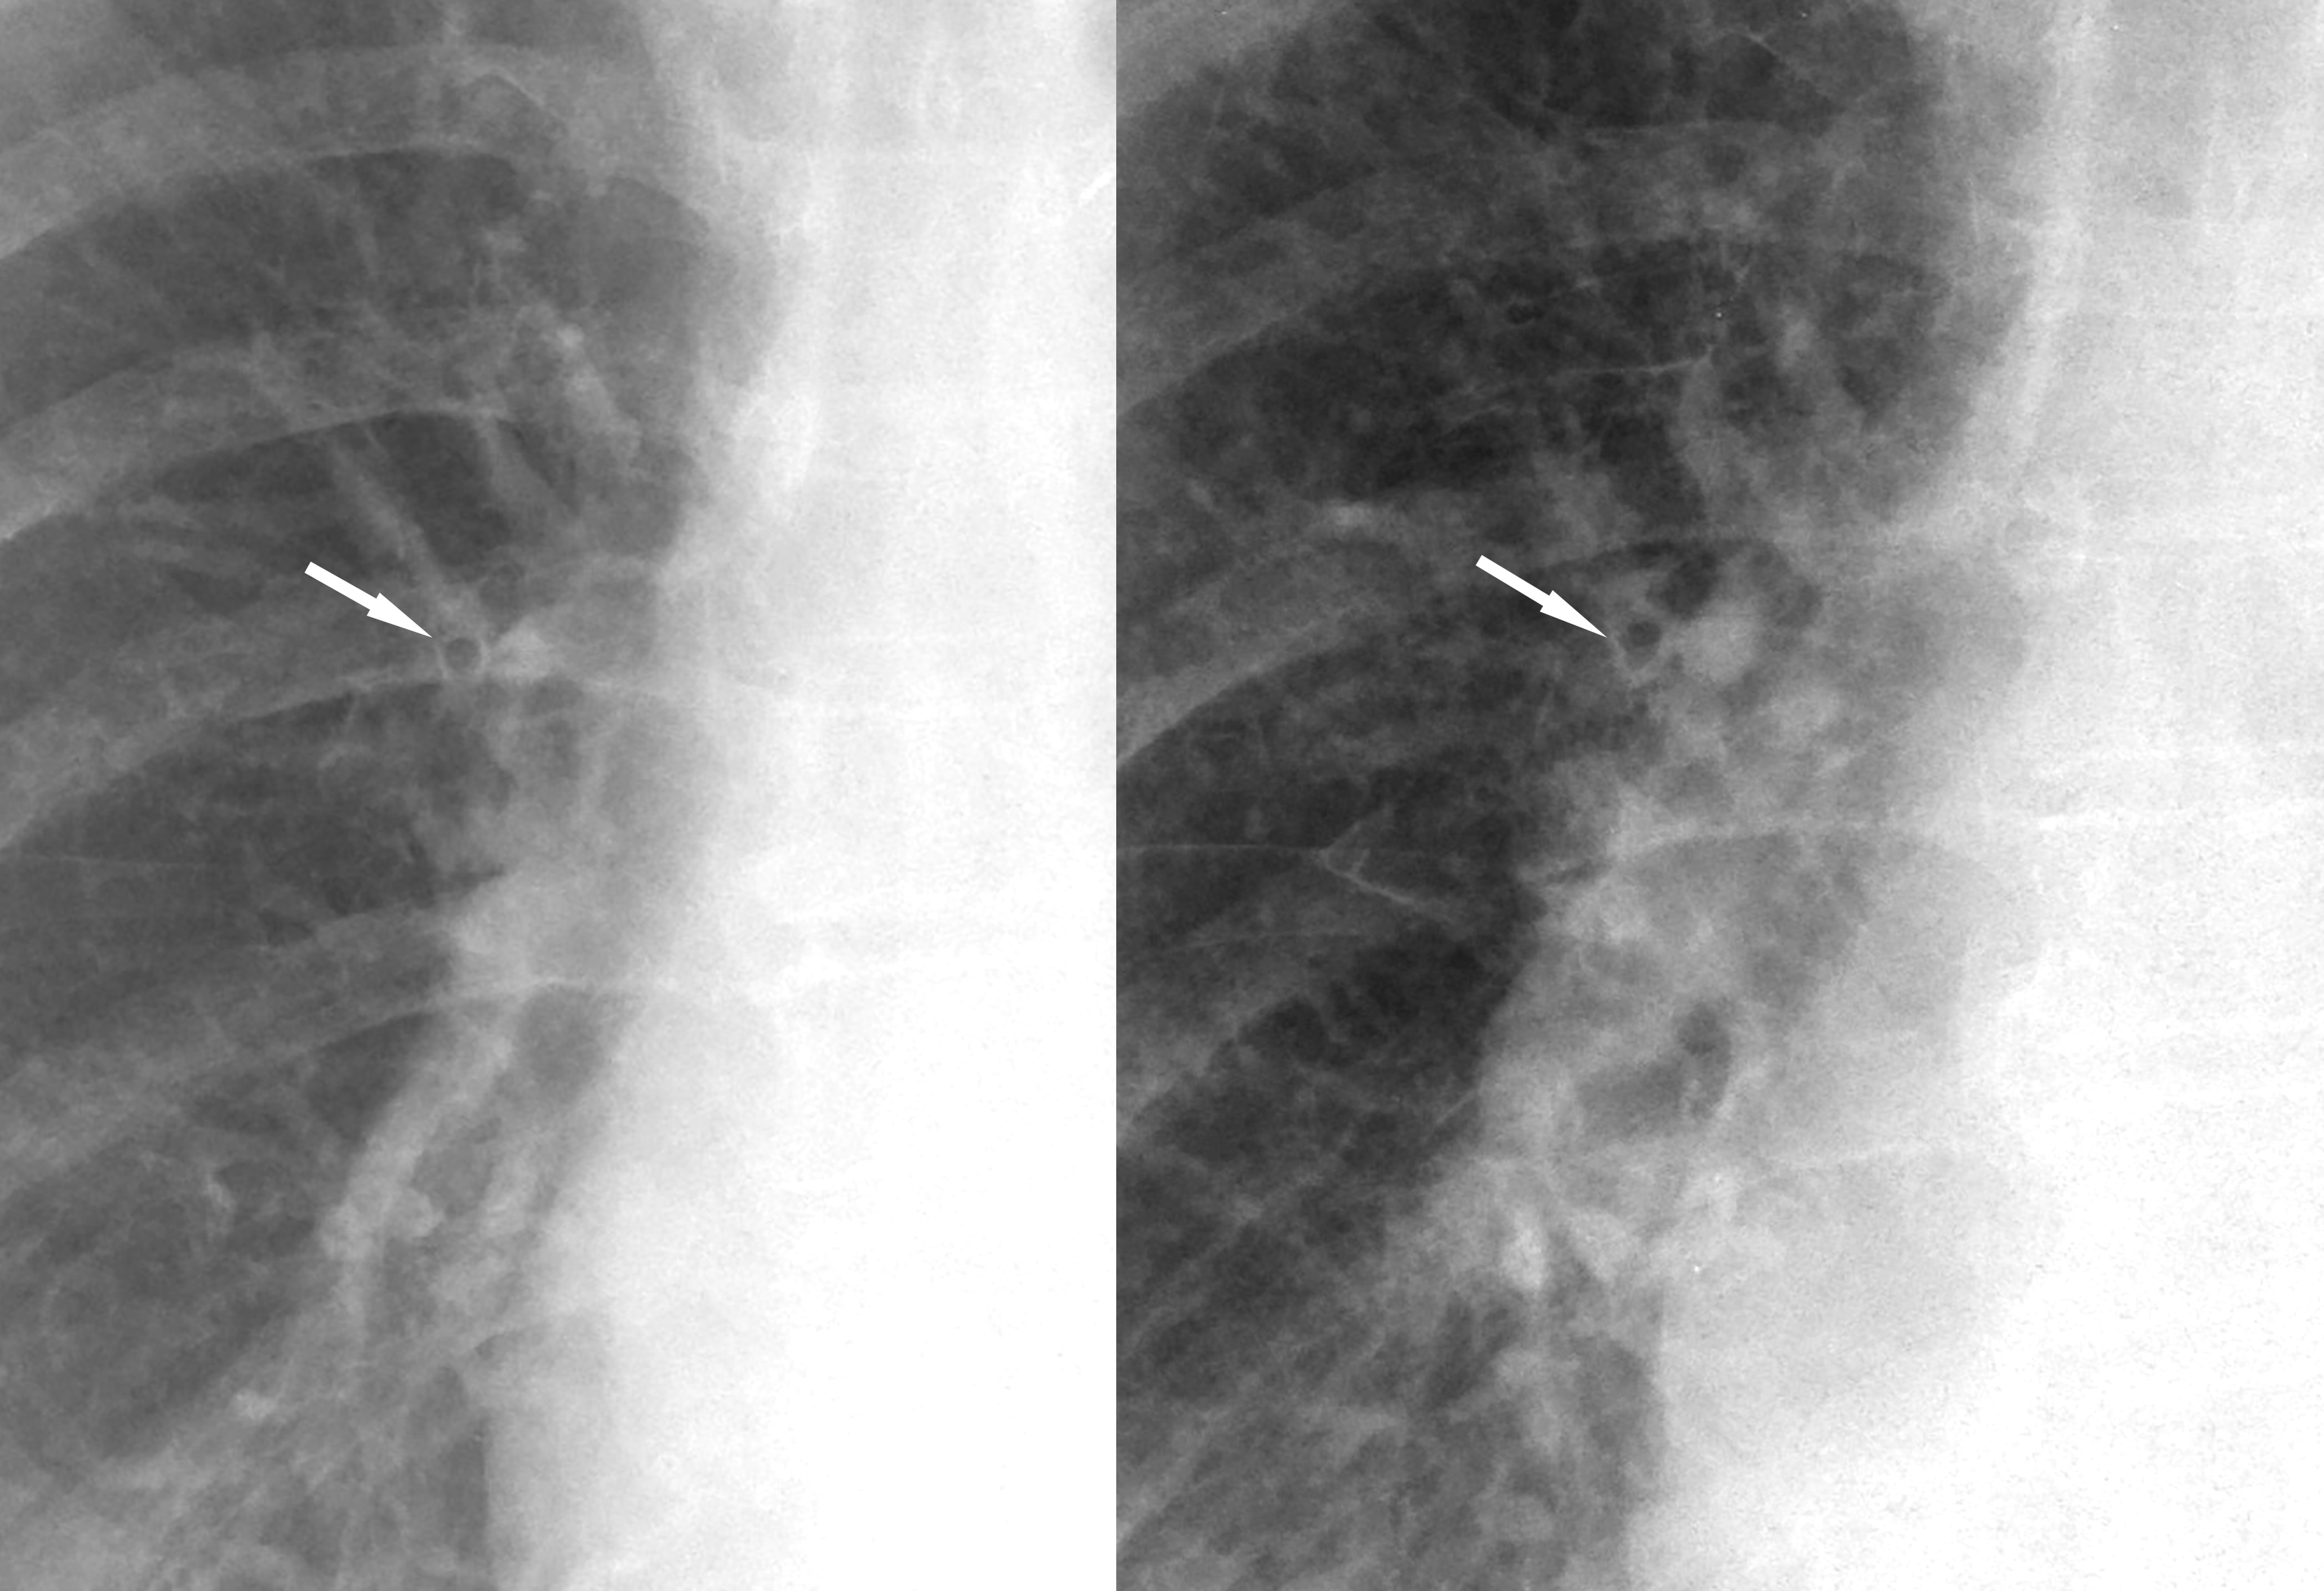

peribronchial cuffing

peribronchial cuffing bef and after